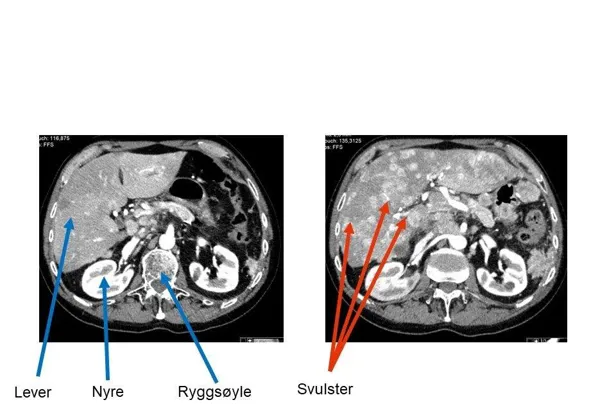

Røntgenundersøkelser

Ved hjelp av disse undersøkelsene kan en svulst påvises. Noen ganger kan imidlertid svulstene være såpass små, eller ligge slik til, at de ikke identifiseres på røntgenundersøkelsene. Ofte må det brukes kontrast på CT undersøkelsene for at svulsten skal oppdages (intravenøs kontrast i arteriell og portovenøs fase).

Likeledes vil MR-oppdage flere svulster og gi bedre tolkningsmuligheter av sykelige forandringer ved bruk av kontrast. MR er bedre til å påvise svulster i skjelettet enn CT.